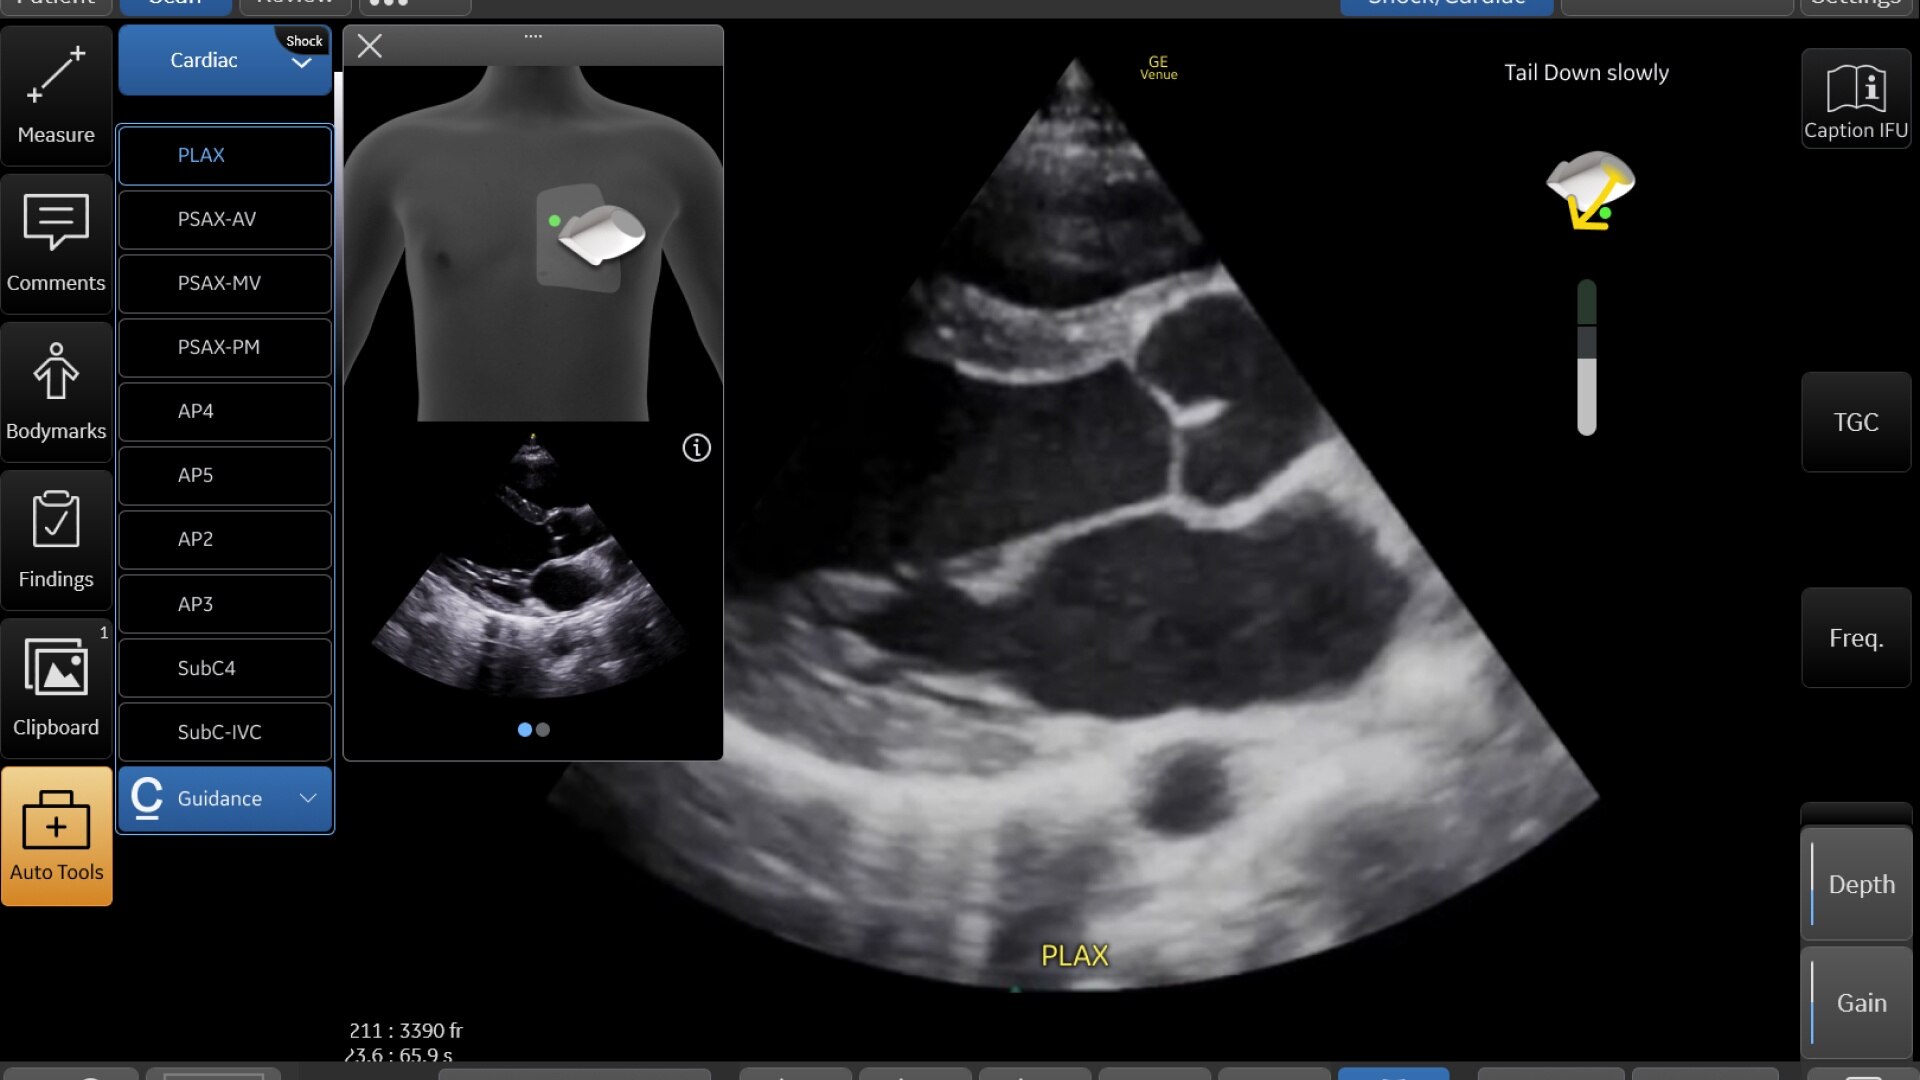

Representación de onda de ECG

Exploraciones cardíacas simplificadas con visualización de la forma de onda